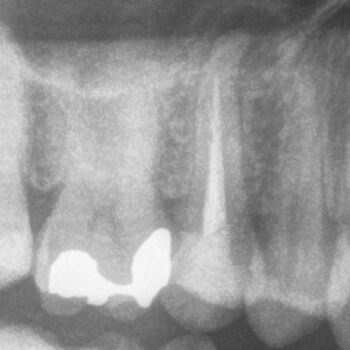

Fall 2: Entfernung eines Instrumentenfragmentes

Röntgenbild: Instrumentenfragment Ausgangssituation

Ausgangssituation

Röntgenbild: Instrumentenfragment Kontrolle nach Wurzelfüllung

Kontrolle nach Wurzelfüllung